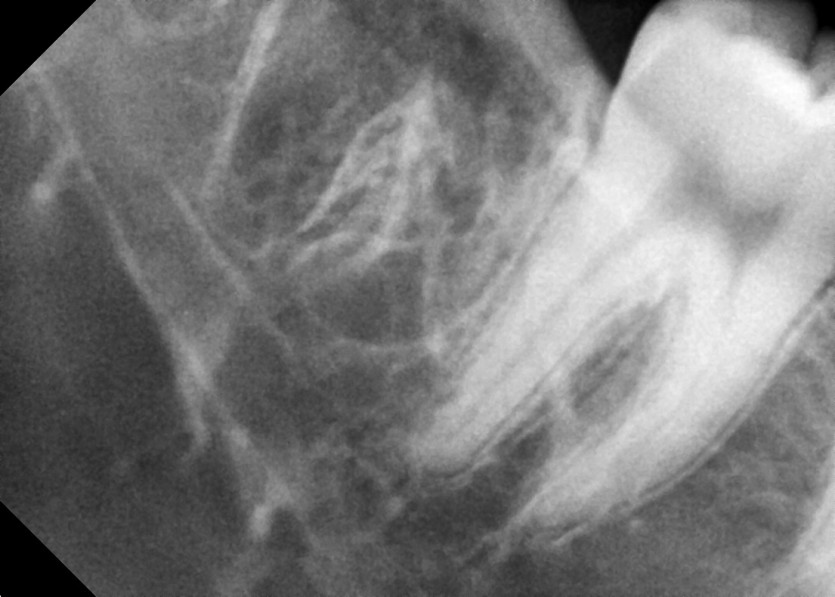

#18,48 사랑니 발치

#48 사랑니 발치

구강외과 전문의가 당일 발치했습니다.